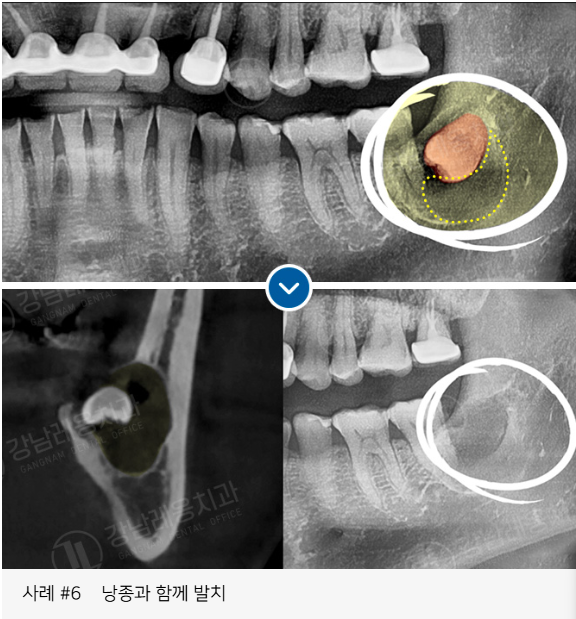

✅ 염증이나 낭종을 동반된 경우

사랑니 발치로 강남레옹치과에 방문해주시는

40~50%가 수평/매복 사랑니이며

아래와 같은 고난도 케이스도

충분한 상담을 통해

사랑니 진료를 진행하고 있습니다.